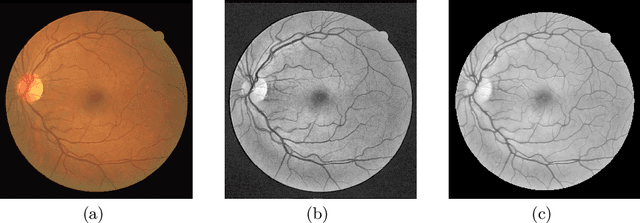

Abstract:Fundus photography and Optical Coherence Tomography Angiography (OCT-A) are two commonly used modalities in ophthalmic imaging. With the development of deep learning algorithms, fundus image processing, especially retinal vessel segmentation, has been extensively studied. Built upon the known operator theory, interpretable deep network pipelines with well-defined modules have been constructed on fundus images. In this work, we firstly train a modularized network pipeline for the task of retinal vessel segmentation on the fundus database DRIVE. The pretrained preprocessing module from the pipeline is then directly transferred onto OCT-A data for image quality enhancement without further fine-tuning. Output images show that the preprocessing net can balance the contrast, suppress noise and thereby produce vessel trees with improved connectivity in both image modalities. The visual impression is confirmed by an observer study with five OCT-A experts. Statistics of the grades by the experts indicate that the transferred module improves both the image quality and the diagnostic quality. Our work provides an example that modules within network pipelines that are built upon the known operator theory facilitate cross-modality reuse without additional training or transfer learning.

Abstract:Deep neural networks have achieved tremendous success in various fields including medical image segmentation. However, they have long been criticized for being a black-box, in that interpretation, understanding and correcting architectures is difficult as there is no general theory for deep neural network design. Previously, precision learning was proposed to fuse deep architectures and traditional approaches. Deep networks constructed in this way benefit from the original known operator, have fewer parameters, and improved interpretability. However, they do not yield state-of-the-art performance in all applications. In this paper, we propose to analyze deep networks using known operators, by adopting a divide-and-conquer strategy to replace network components, whilst retaining its performance. The task of retinal vessel segmentation is investigated for this purpose. We start with a high-performance U-Net and show by step-by-step conversion that we are able to divide the network into modules of known operators. The results indicate that a combination of a trainable guided filter and a trainable version of the Frangi filter yields a performance at the level of U-Net (AUC 0.974 vs. 0.972) with a tremendous reduction in parameters (111,536 vs. 9,575). In addition, the trained layers can be mapped back into their original algorithmic interpretation and analyzed using standard tools of signal processing.

Abstract:In this paper, we reformulate the conventional 2-D Frangi vesselness measure into a pre-weighted neural network ("Frangi-Net"), and illustrate that the Frangi-Net is equivalent to the original Frangi filter. Furthermore, we show that, as a neural network, Frangi-Net is trainable. We evaluate the proposed method on a set of 45 high resolution fundus images. After fine-tuning, we observe both qualitative and quantitative improvements in the segmentation quality compared to the original Frangi measure, with an increase up to $17\%$ in F1 score.